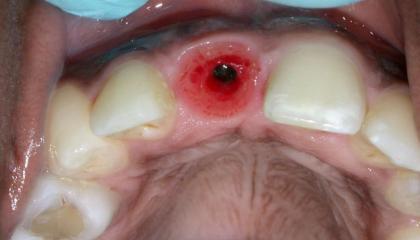

After

Single Dental Implant